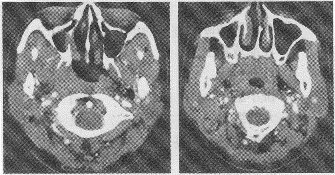

2.患者已行颈部CT扫描,主要图像如下,结合CT表现,最可能的诊断为

正确答案:1.C;2.C;3.ABCDE;4.ABCE;5.C 解题思路:鼻咽癌好发于40~60岁者,男性多于女性,已知的发病因素有种族、家族因素,EB病毒感染及环境致癌因素。本病特点是早期症状隐蔽,常因广泛浸润周围组织及发生淋巴结转移后才发现,主要症状有鼻阻塞、鼻衄、耳鸣、耳闷塞及听力减退,鼻咽及其邻近结构如鼻及鼻窦肿瘤均可有以上症状,CT表现有鼻咽变形、不对称、咽隐窝消失,鼻咽侧壁软组织肿块,淋巴结转移多见于颈深淋巴结、咽后外侧淋巴结。MRI对鉴别肿瘤复发有重要价值,正确率可达80%以上。